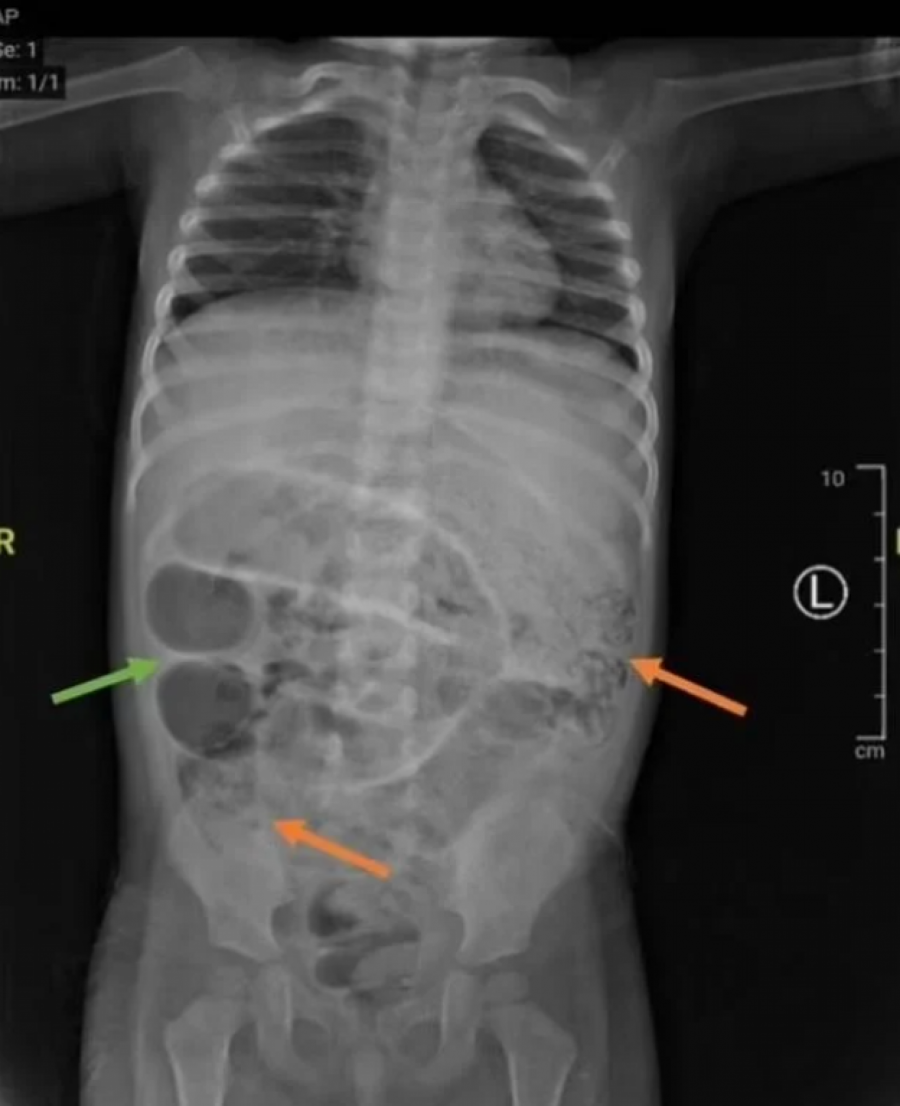

Dijagnoza je, prema rečima medicinskog osoblja, u početku bila blokada creva.

Tokom operacije, lekari su identifikovali i uklonili brojne crve Ascaris lumbricoides , dugačke nekoliko centimetara, koji su stvorili "gužvu" u tankom crevu deteta.

- Rez napravljen za uklanjanje parazita napravljen je na tački otprilike 50 centimetara od debelog creva. Crvi su poslati na dalju analizu u laboratoriju. Istovremeno, analize krvi su pokazale da dete boluje i od anemije, česte pojave u ovakvim slučajevima. Paraziti apsorbuju značajan deo gvožđa i drugih hranljivih materija u telu, uzrokujući, između ostalog, probleme u razvoju deteta. Mladom pacijentu je određena terapija antibioticima, hidratantnim rastvorima i preparatima protiv crevnih parazita. Otpušten je nedelju dana kasnije - prenose mediji.